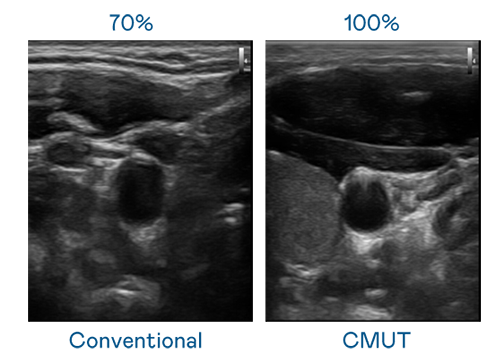

CMUT 技術是一種用電容式微機電元件來產生超音波訊號的技術。與傳統 PZT 壓電式技術相比,CMUT 頻寬增加 30%,更寬頻的超音波訊號讓影像解析度大幅提升,是實現高影像品質醫療超音波掃描、促進精準醫療發展的關鍵技術。

超音波影像的解析度高低,首先取決於探頭能發出的訊號頻寬。mile米乐 CMUT 可提供高清晰的超音波訊號,提供高頻寬、高靈敏度、影像紋理細節更高的超音波影像,協助醫護人員縮短影像判讀時間及利用精準的醫療影像進行診斷。